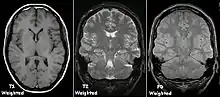

T1 and T2

Each tissue returns to its equilibrium state after excitation by the independent relaxation processes of T1 (spin-lattice; that is, magnetization in the same direction as the static magnetic field) and T2 (spin-spin; transverse to the static magnetic field). To create a T1-weighted image, magnetization is allowed to recover before measuring the MR signal by changing the repetition time (TR). This image weighting is useful for assessing the cerebral cortex, identifying fatty tissue, characterizing focal liver lesions, and in general, obtaining morphological information, as well as for post-contrast imaging. To create a T2-weighted image, magnetization is allowed to decay before measuring the MR signal by changing the echo time (TE). This image weighting is useful for detecting edema and inflammation, revealing white matter lesions, and assessing zonal anatomy in the prostate and uterus.

The standard display of MRI images is to represent fluid characteristics in black and white images, where different tissues turn out as follows: